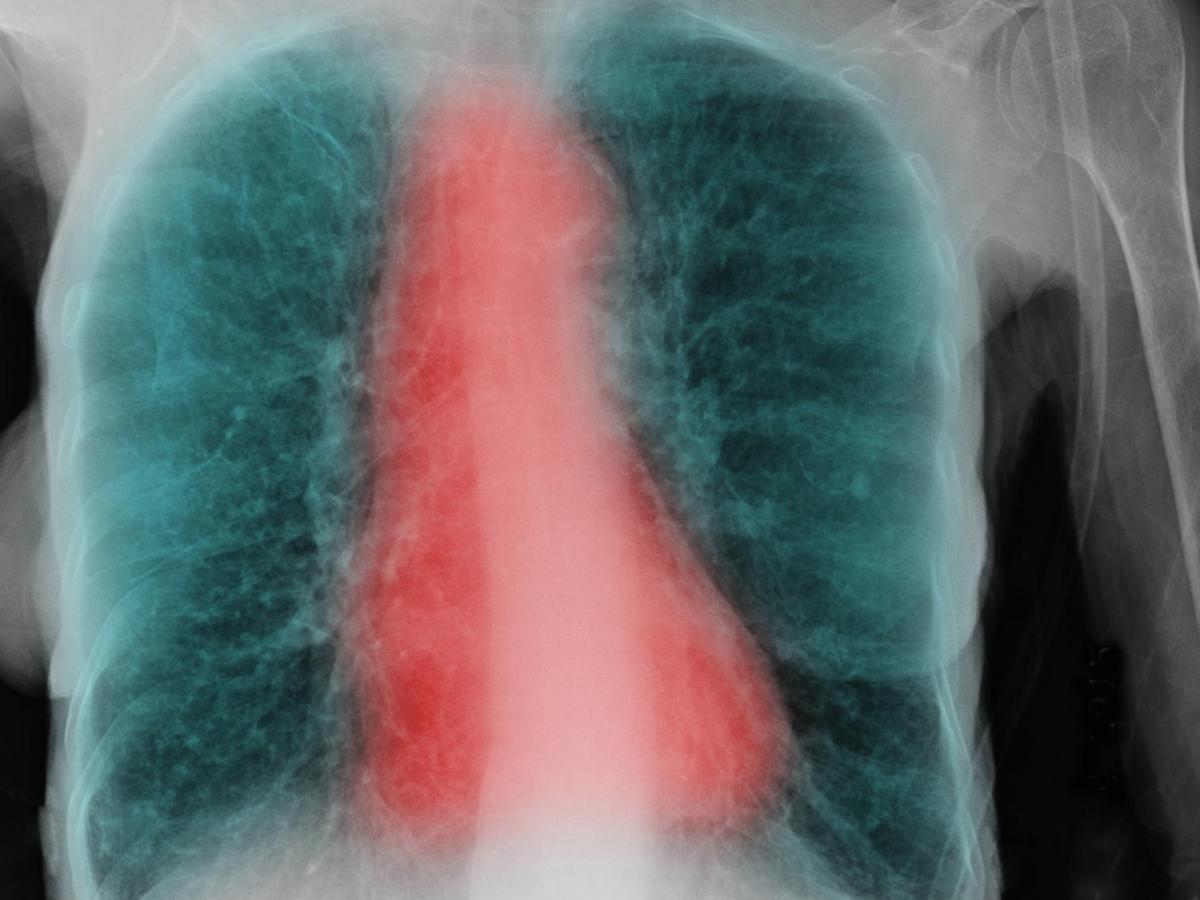

Ces scans des voies aériennes (en rouge) et des poumons (en noir) montrent le spectre de la dysanapsie, avec des voies aériennes plus petites en proportion de la taille des poumons (gauche) par rapport aux voies aériennes de taille normale (milieu), et plus grandes que les voies aériennes normales (droite). Cliquez pour voir en plus grand. Crédit: VIDA Apollo Software, courtesy of Eric A. Hoffman, PhD, Radiology, University of Iowa Carver College of Medicine.